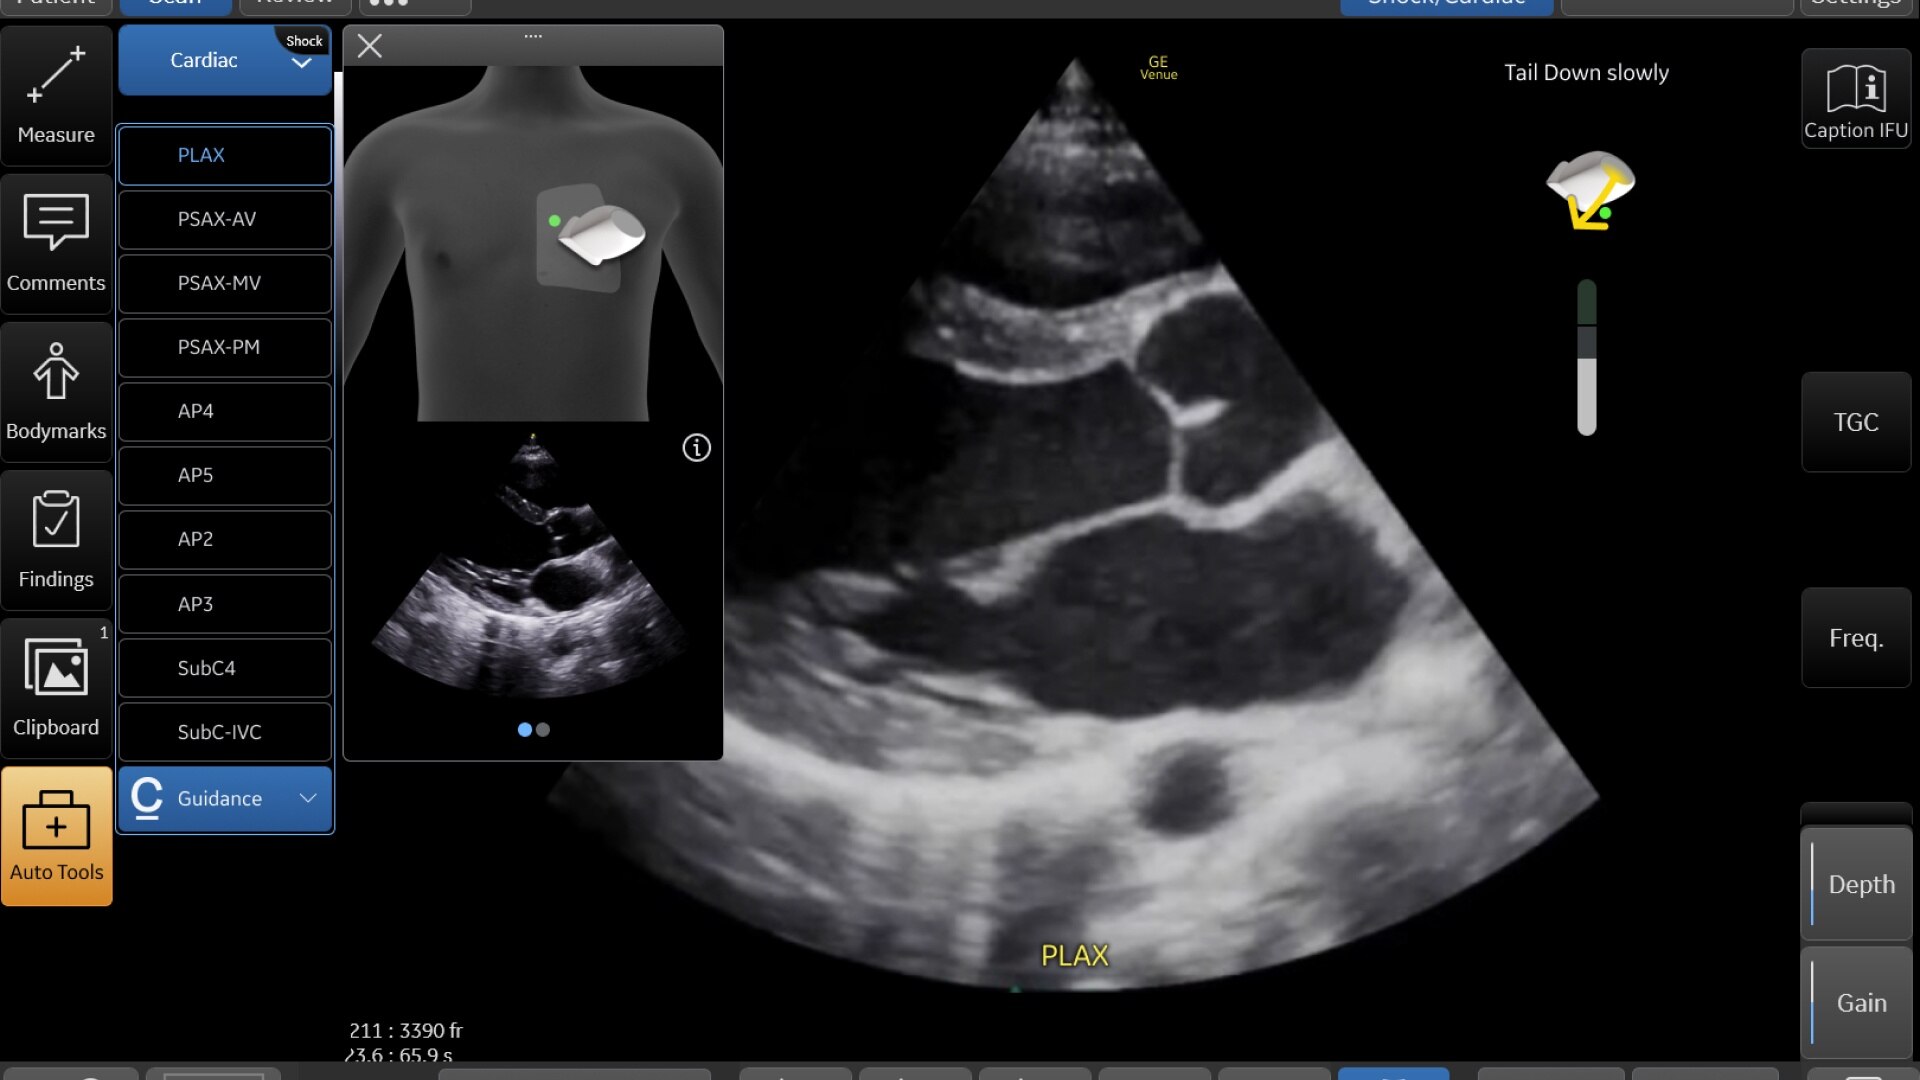

AI-DRIVEN AUTO TOOLS

Advanced and automated clinical tools enabling you to quickly diagnose, treat and determine a care pathway.

Venue Go has been designed and tested to be walk up easy for novice to expert users, and it features a number of AI-enabled automated tools to accelerate clinical workflow while also reducing the fatigue of repeated and difficult tasks. Utilizing proprietary algorithms, we synthesize data from numerous patients to ensure accurate calculations for clinical confidence.